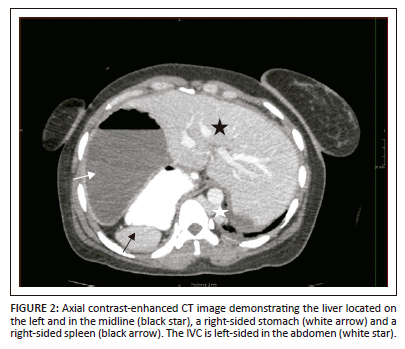

A CT of the abdomen revealed right-sided polysplenia (Figure 1) with a dominant parent spleen, a left-sided liver, extending across the midline, and a right-sided stomach (Figure 2). The superior mesenteric artery and vein were parallel to one another (Figure 3). The duodenum coursed anterior to the portosplenic vein with the duodenojejunal junction located to the left of the left-sided vertebral body pedicle but inferior to the level of the duodenal bulb, in keeping with some degree of malrotation. The jejunal loops were located in the left side of the abdomen. There was twisting of the mesentery in the right lower quadrant (Figure 4) with small bowel dilatation and massive dilatation of the caecum and proximal ascending colon (Figure 5). The transition point was within the proximal to mid ascending colon, with collapse of the large bowel distal to this point. There was also dilatation of the small bowel, most likely due to an incompetent ileocecal valve. A small amount of free fluid was noted in the right paracolic gutter and the Pouch of Douglas with multiple mesenteric lymph nodes in the right iliac fossa. Additionally, there was absence of the uncinate process of the pancreas suggestive of a truncated pancreas (Figure 3).

The chest CT demonstrated a left-sided inferior vena cava (IVC) within the abdomen. Above the diaphragm, the IVC crossed the midline and continued into the chest as the azygous vein. There was no hepatic IVC (Figure 6). There was a common origin of the left common carotid artery and brachiocephalic trunk, in keeping with a Bovine aortic arch. The right lung was trilobed with an eparterial bronchus. The left lung was bilobed with a hyparterial bronchus.